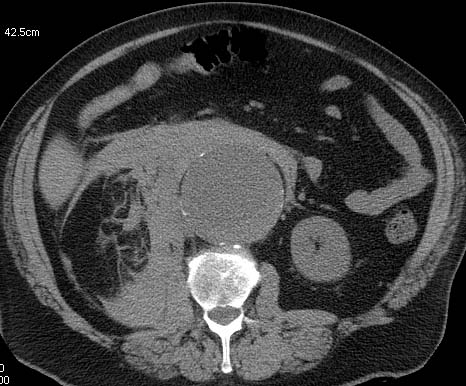

Malgré ces écueils assumés, c'est sur ce principe, qu'une équipe londonienne s'est basée pour juger des résultats de la prise en charge des ruptures d'anévrysme de l'aorte (RAAA) abdominale en Angleterre et aux Etats-Unis.

A partir des données de l'ensemble des hôpitaux anglais et d'un échantillon représentatif de 20 % des dossiers de sortie des hôpitaux des Etats-Unis sur les années 2005 à 2010, Alan Karthikesalingam et coll. ont pu comparer le pronostic des RAAA dans les deux pays.